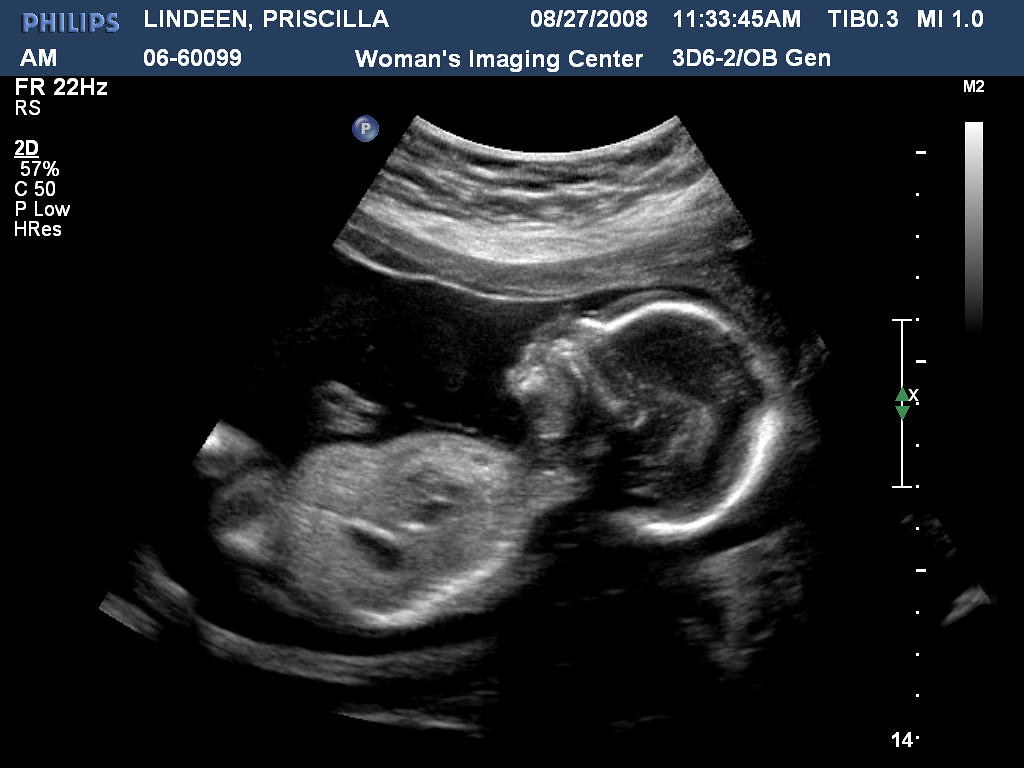

It's a boy Ultrasound 20 weeks Due date Jan. 16th Priscilla Flickr How To Read Baby Boy Ultrasound Discover what your baby boy's ultrasound will look like at different stages of pregnancy and learn some interesting facts about the making of a boy. Try to identify the scrotum and testicle of a male, with the help of the technician. Identifying the foetal genitalia is one aspect of interpreting ultrasound images that allows parents to learn their baby’s gender.. How To Read Baby Boy Ultrasound.